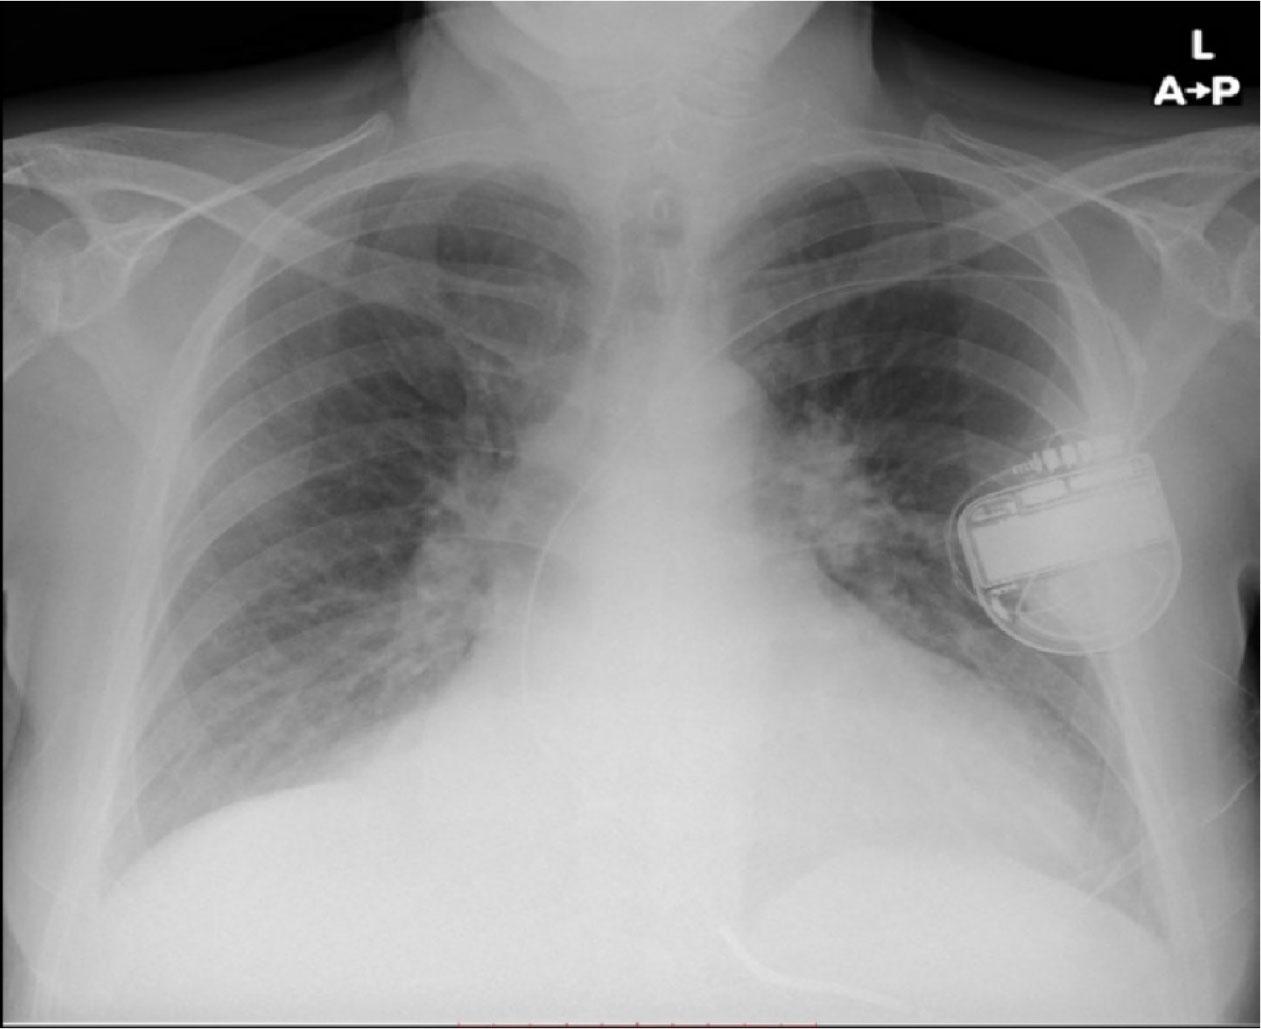

The patient experienced multiple previous hospitalizations for acute decompensated heart failure, with the most recent in January 2023. Upon admission to our institution, he exhibited severe exertional dyspnea, hypotension (BP 92/71 mmHg), tachycardia (HR 118 bpm), and signs of low cardiac output. Laboratory studies revealed elevated lactate and bilirubin levels, indicating metabolic acidosis and early multiorgan dysfunction. Chest radiography showed cardiomegaly without pulmonary consolidation (Figure 1).

Chest radiography on admission: Marked cardiomegaly with increased interstitial markings, permanent ICD device in situ, without evidence of pulmonary consolidation or pleural effusion